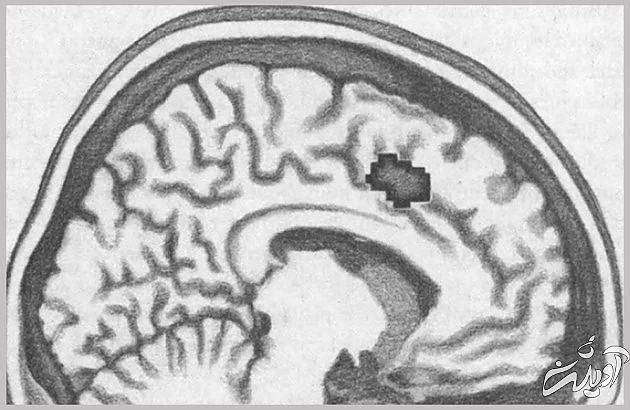

این ایده، که تنهایی را به درد اجتماعی مرتبط میکند، از استعاره فراتر میرود. تصویرسازی تشدید مغناطیس کارکردی (افامآرآی) نشان میدهد قسمت مربوط به عواطف مغز، که هنگام طرد شدن فعال میشود، سینگولیت قدامی فوقانی۸، همانی است که واکنشهای حسی به درد جسمانی را ثبت میکند.

بعد از کشف اینکه هنگام احساس طرد اجتماعی (انزوا) و واکنش در برابر درد جسمی، افزار واحدی در مغزمان به کار میافتد، رفتهرفته درک میکنیم که چرا نمیتوان صرفاً با «بیرونآمدن از حصار خود»، کمکردن وزن، تغییر ظاهر طبق مد روز یا آشناشدن با آقا یا خانمی مناسب، از دست تنهایی مزمن خلاص شد. درد و رنج تنهایی زخمی است که میتواند به اختلالات عمیقی دامن بزند. این اختلالات، که هم فیزیولوژیکاند و هم رفتاری، قادرند نیاز برآورده نشدۀ ارتباط با دیگران را به ناخوشی مزمن تبدیل کنند و اگر چنین وضعیتی پیش بیاید، برای بهبود بخشیدن به اوضاع، باید ژرفا و پیچیدگی کاملِ نقش تنهایی در زیست و تاریخ تکامل انسان را در نظر بگیریم. اگر راه کیتی بیشاپ را در پیش بگیریم و بکوشیم با خوراکیهای چرب و بازگشت به جمع رفقا حالمان را بهتر کنیم، فقط باعث بدتر شدن اوضاع خواهیم شد.

منطقهای از مغز که به درد جسمانی واکنش نشان میدهد.